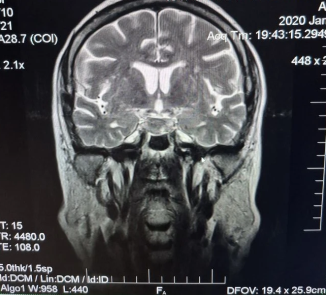

Анамнез заболевания: со слов сына (в сопровождении которого была на приеме), 29.01.2020 пациентка в связи с жалобами на головокружение и слабость самостоятельно прошла МРТ головного мозга (рис. 1, рис. 2, рис. 3).

Рис. 1. МРТ головного мозга (T1 sag sella)

Рис. 2. МРТ головного мозга (T2 Cor)